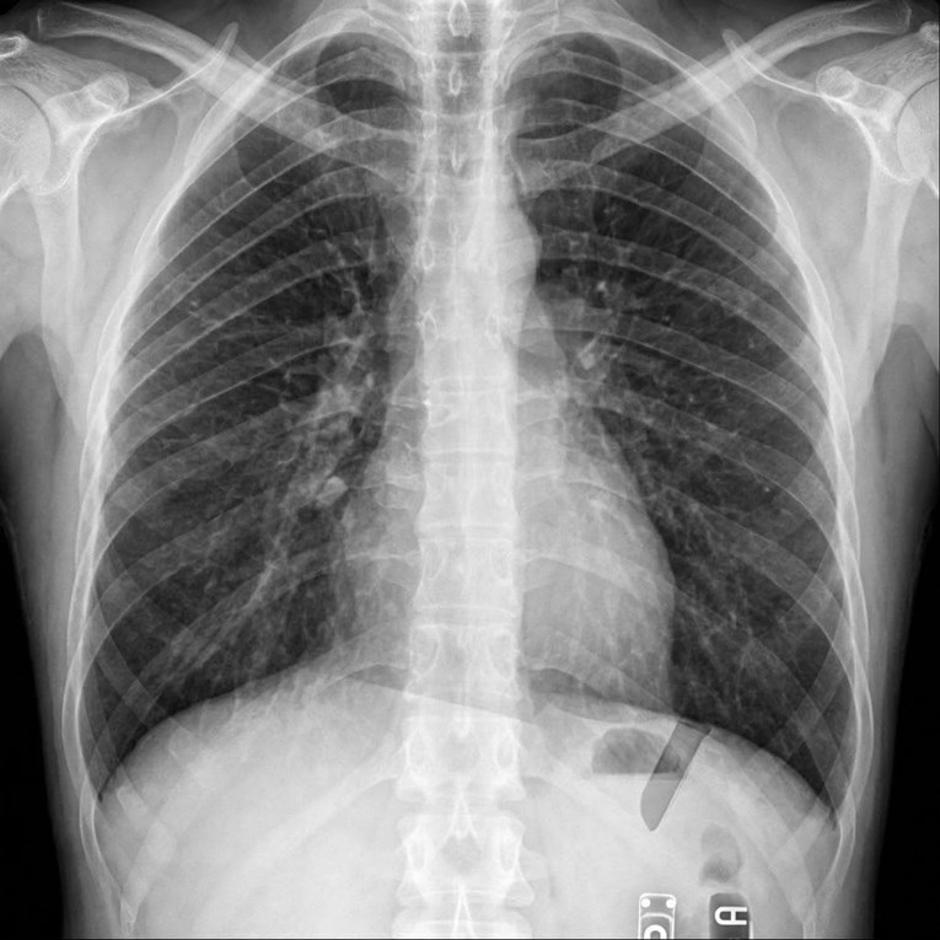

Rendgenska snimka prsnog koša otkrila je bizaran uzrok njegovih tegoba - jedan od izvađenih umnjaka završio mu je u plućima.

Snimka je potvrdila sumnju - umnjak mu je doista završio u plućima. Liječnici su mu objasnili da pacijent u takvoj situaciji obično zakašlje ili proguta zub, no kako je Artur bio pod sedacijom, taj refleks nije radio.